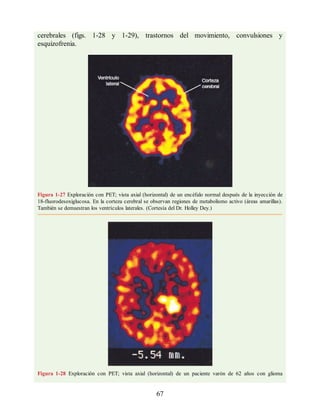

aneurisma congénito en el polígono arterial cerebral (polígono de Willis) o, con menor

frecuencia, por una malformación arteriovenosa. Los síntomas, que tienen un

comienzo súbito, incluyen cefalea intensa, rigidez de nuca y pérdida de consciencia. El

diagnóstico se establece por TC o RM o al extraer líquido cefalorraquídeo